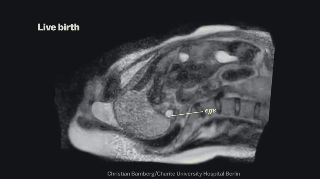

7. Un feto a punto de salir al mundo.